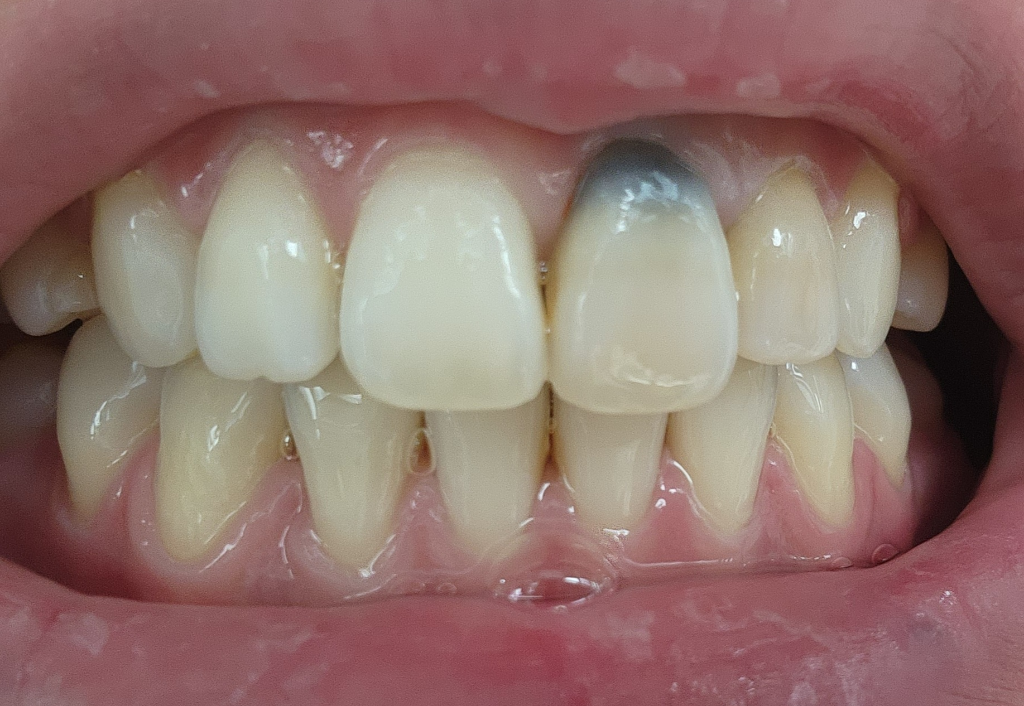

오래전 검은색으로 변색된 저 치아와 바로옆 작은 앞니가 같이 빠진적이 있습니다. 그래서 신경치료를 진행했었는데 점점 큰앞니만 변색되기 시작했습니다.

그래서 신경치료했던것을 다 긁어낸 후 다시 신경치료하고 그 이후 실활치미백을 진행했고, 9월-10월 사이 3번의 미백치료로 밝아진 줄 알았으나 12월쯤 다시 어두워지기 시작해 한번 더 받아 총 4번의 미백을 진행했습니다.

이제 모든 치료가 다 끝난 줄 알았으나, 2달도 채 되지않아 다시 어두워지고 있는 느낌이 들어 다시 상담을 받았고, 원래 실활치미백이 잘 이루어진 경우에는 이렇게 빨리 어두워지지 않는다는 답변을 받았습니다.

이 두사진은 레진으로 덮기 전 상담받는 당시 사진입니다.

상담해주실때, 지금 이정도로 뚫어서 진행을 했었고, 아직도 안쪽에 사진상 보이는 저 검은색 부분이 오염된 부분이며 치아 안쪽을 더 뚫어서 다 제거하기에는 치아 외벽이 거의 남아있지 않아 치아 자체가 부서질 수 있다고 하셨습니다.